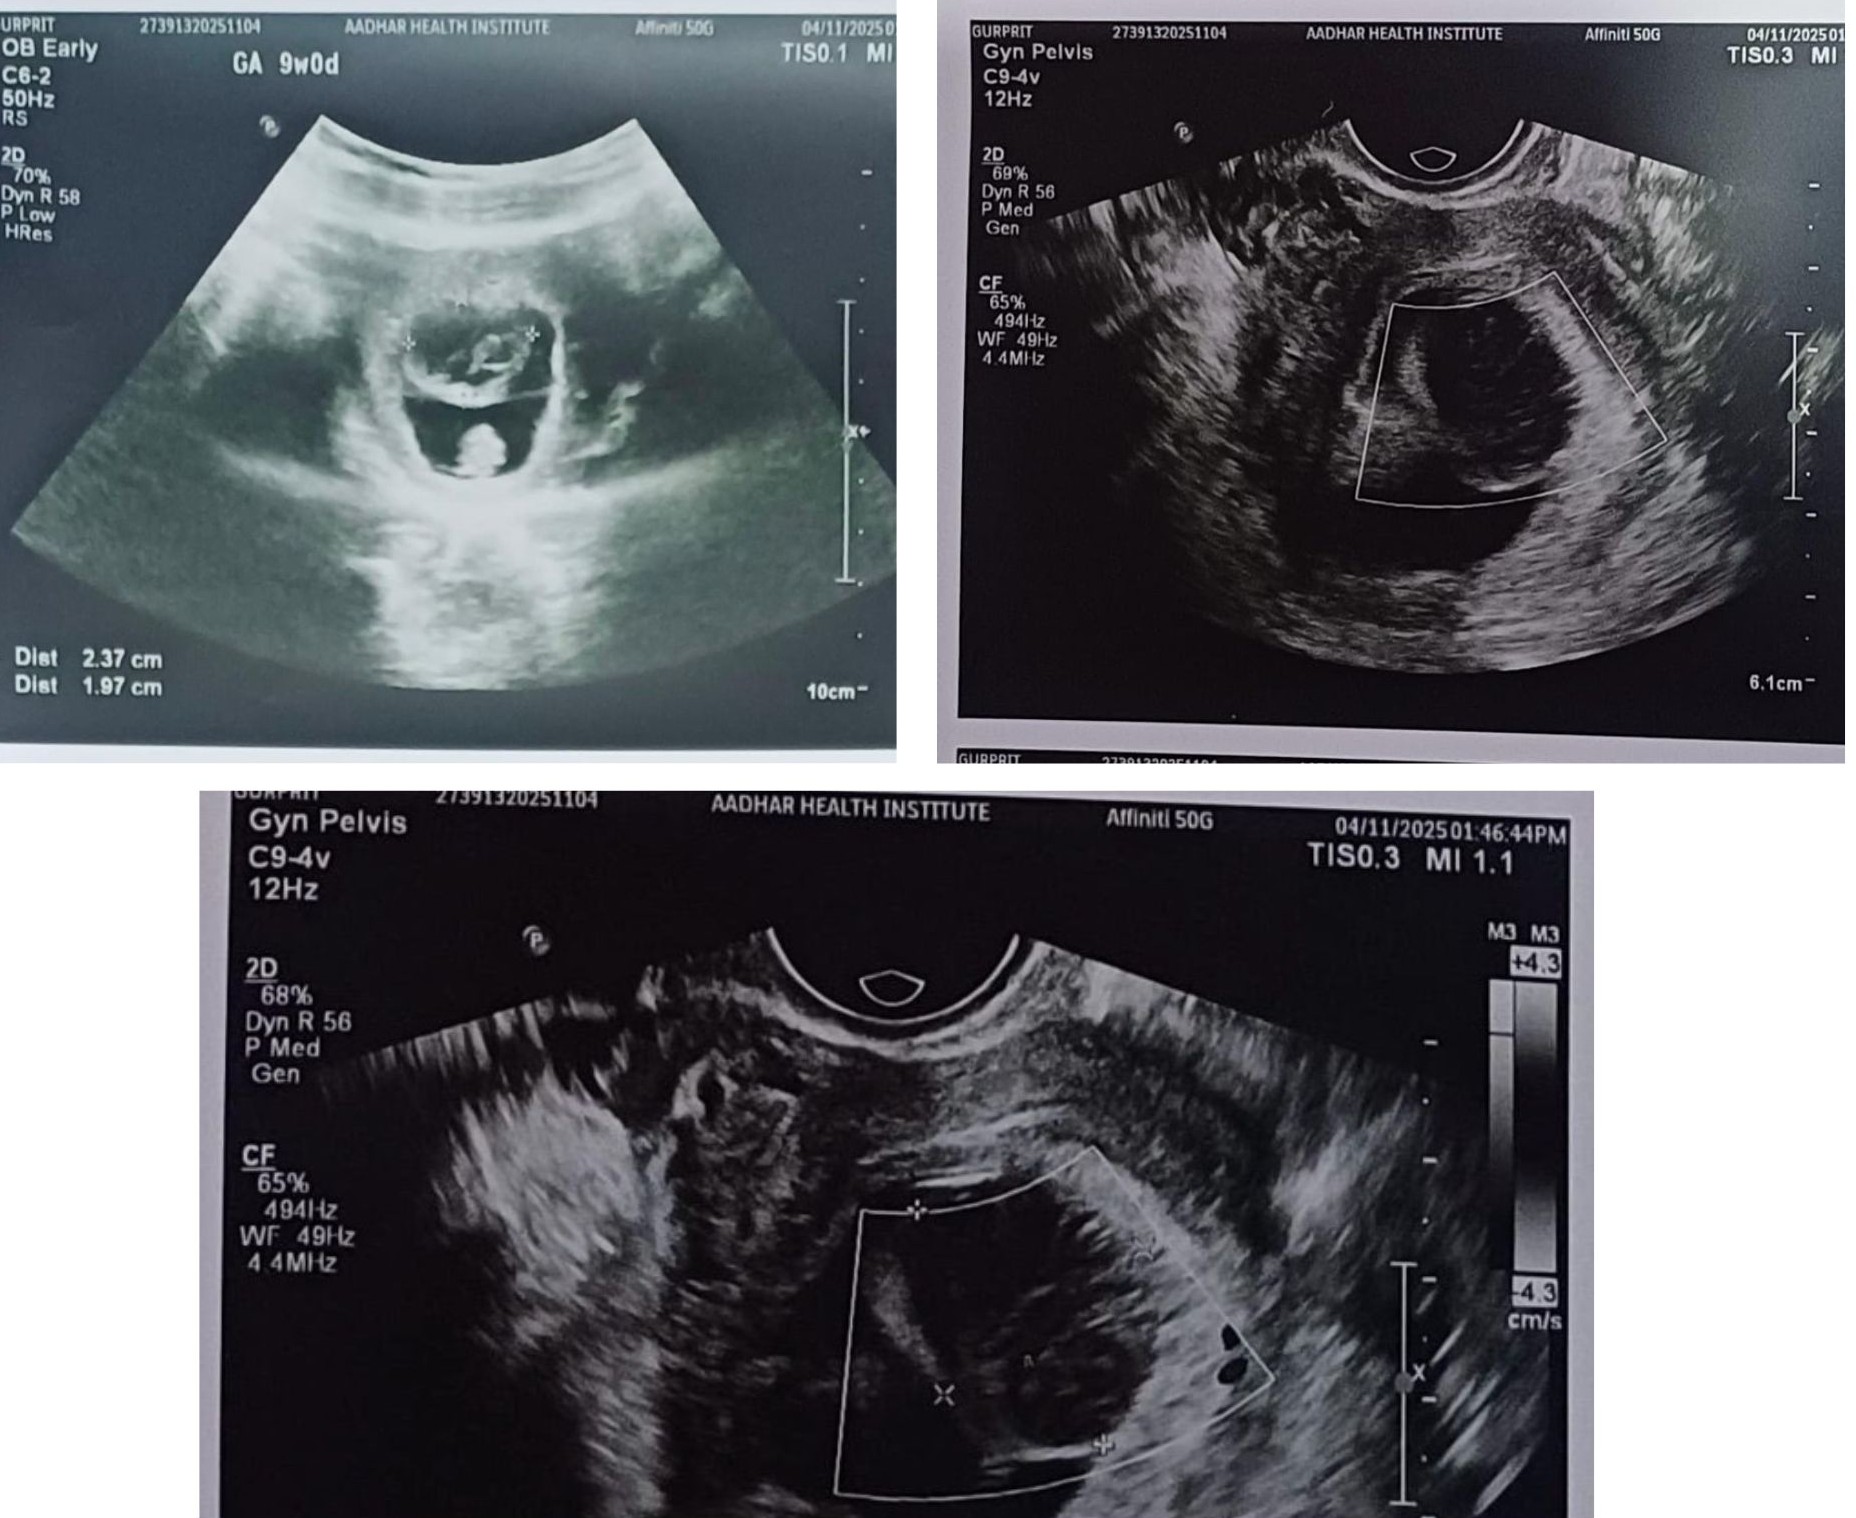

A 28-year-old female presented for a routine early pregnancy ultrasound at 9 weeks of gestation.

Single live intrauterine pregnancy

A well-marginated heteroechoic lesion projecting into the gestational sac from the chorionic wall

Introduction

A chorionic bump is a focal, convex, nodular bulge arising from the chorionic surface and projecting into the gestational sac. It usually shows mixed or hypoechoic internal echoes.

It may represent a small hematoma bulging into the gestational sac or a resorbing anembryonic (failed) second gestation. It is an uncommon ultrasound finding, seen in approximately 0.4–0.7% of pregnancies before 10 weeks.